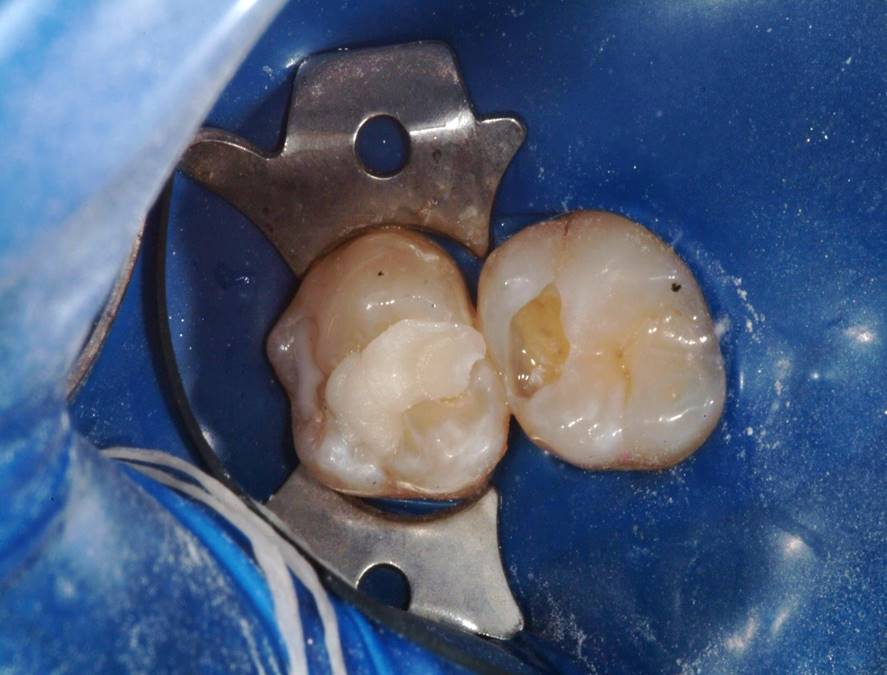

Fig 8. A flowable bulk-fill dentin replacement composite was placed deep into the preparation and adapted to the cavity walls.

Figure 8

Fig 9. View of the flowable bulk-fill dentin replacement increment before light-curing.

Figure 9